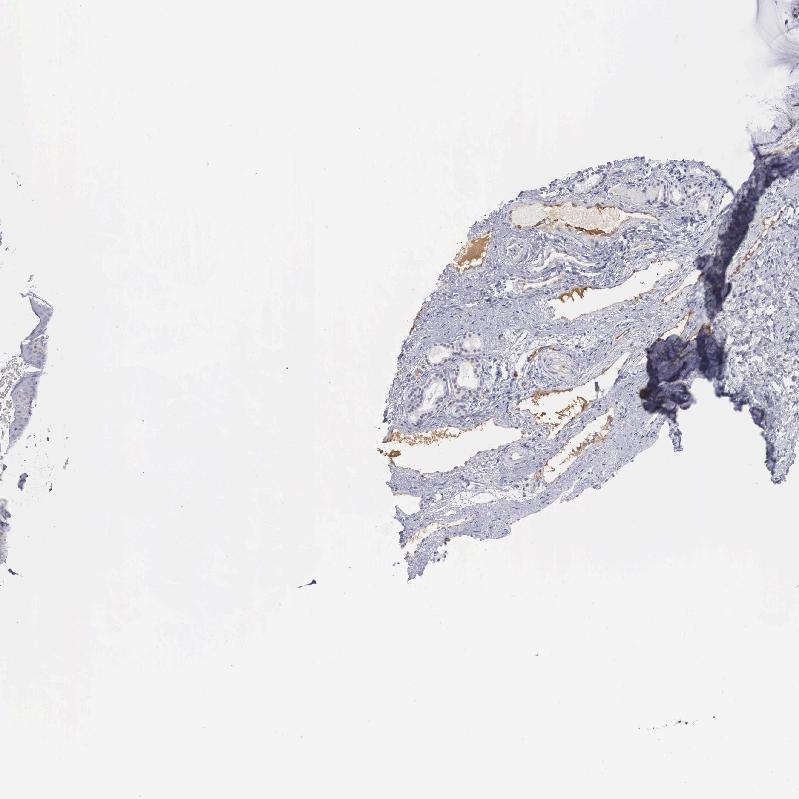

TISSUE PRIMARY DATA NASOPHARYNX Show tissue menu

NASOPHARYNX - Antibody stainingi

Antibody staining in the annotated cell types in the current human tissue is reported as not detected, low, medium, or high, based on conventional immunohistochemistry profiling in selected tissues. This score is based on the combination of the staining intensity and fraction of stained cells.

Each image is clickable and will lead to virtual microscopy that enables deeper exploration of all samples and also displays staining intensity scores, fraction scores and subcellular localization as well as patient and tissue information for each sample.

Antibody HPA000251

Respiratory epithelial cells Not detected